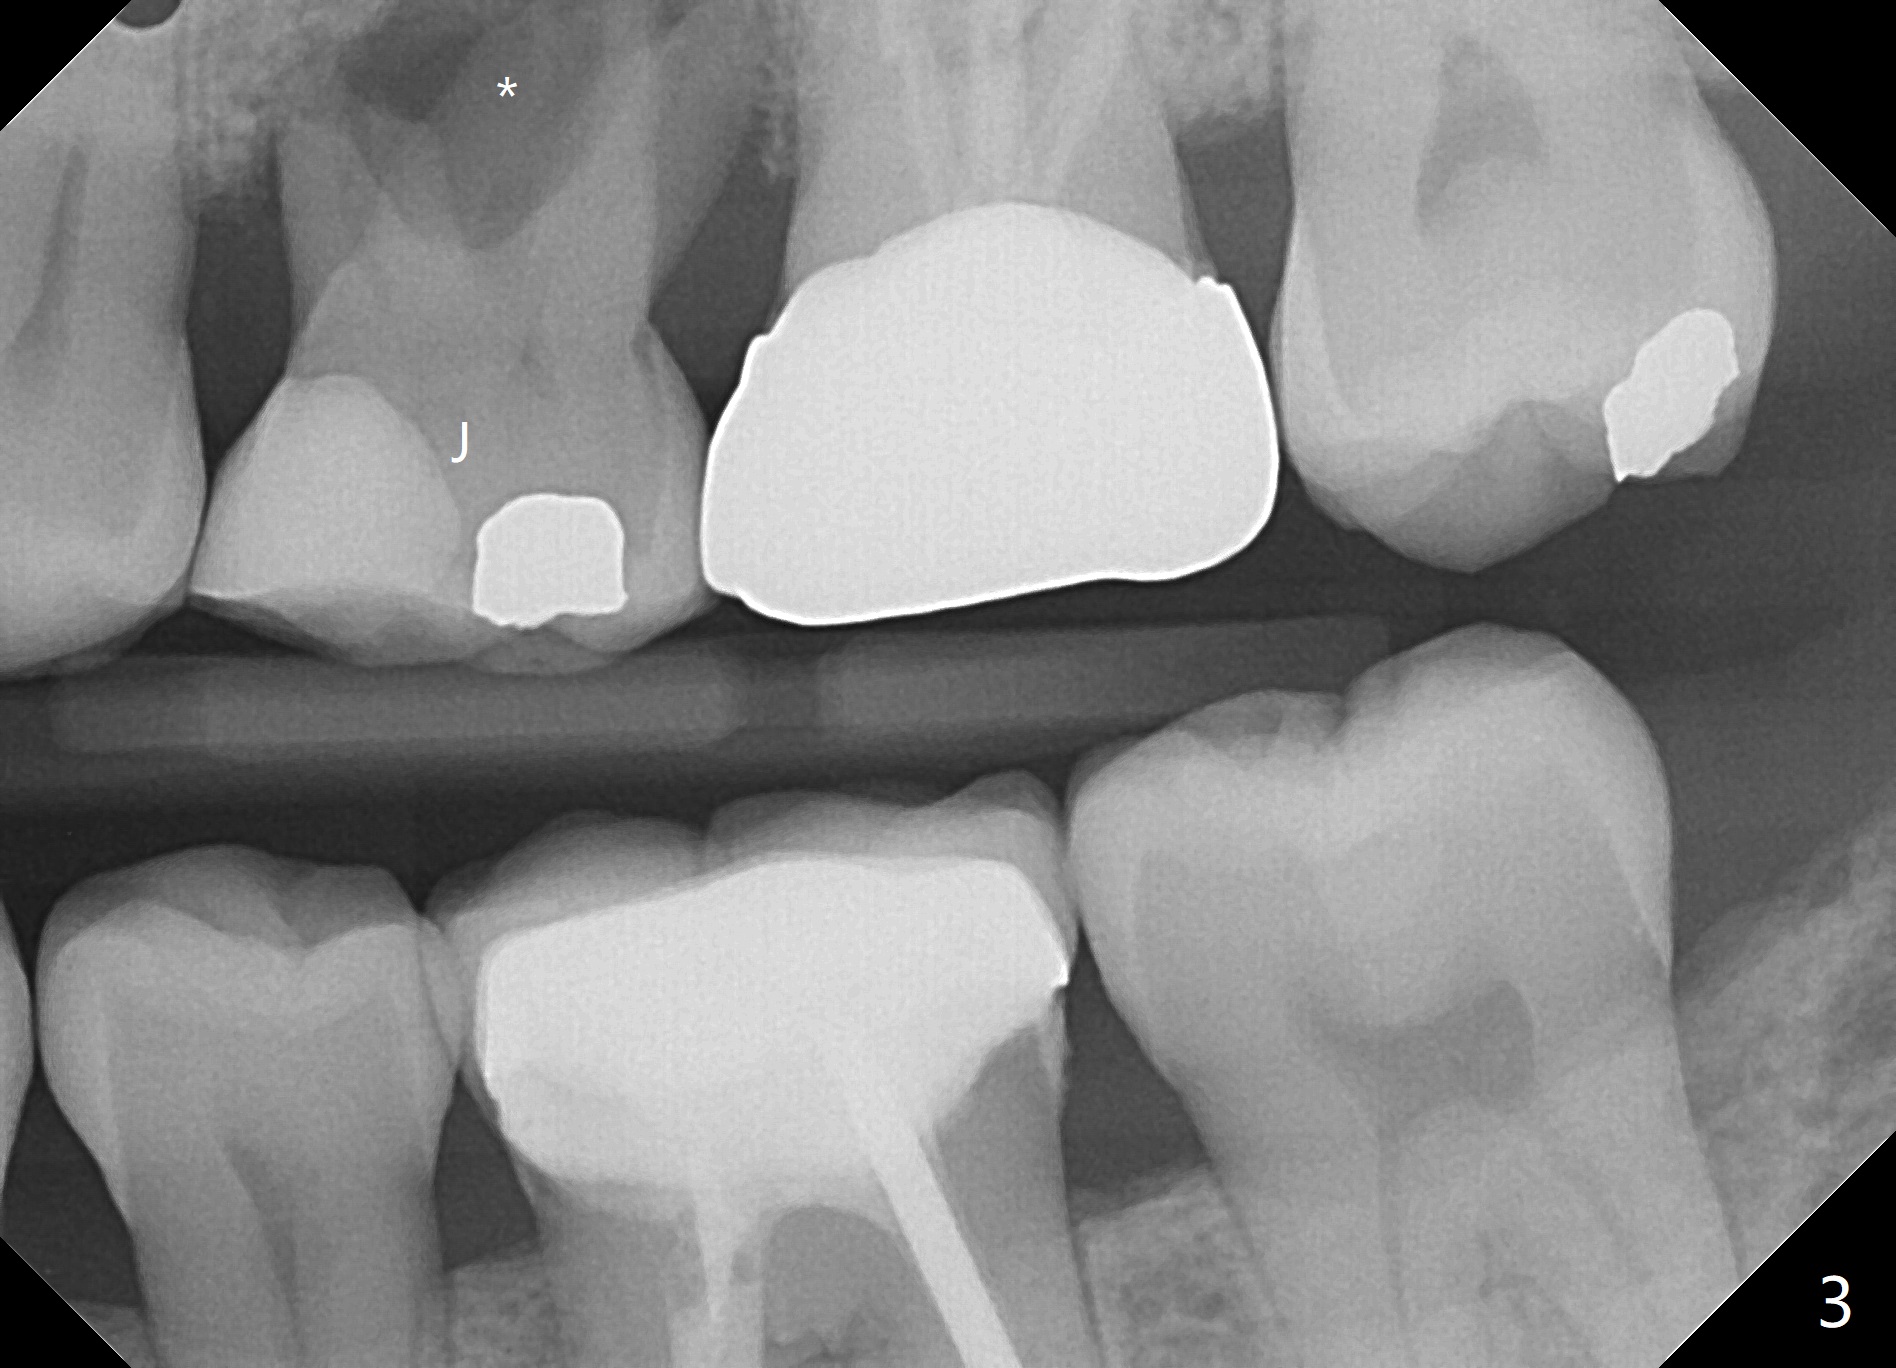

A 42-year-old woman requests extraction of the upper left 2nd primary molar with abscess (Fig.1,3,4). To avoid implants (for #30 as well in Fig.2) and improves cosmetics (anterior crowding), she chooses orthodontics with extraction of 2 more teeth in the other 2 quadrants. It seems necessary to have socket preservation so that the neighboring teeth have the bone to move to (Fig.5 without buccal plate collapse). In fact the coronal half of the buccal plate is resorbed. The bone regeneration is also important in case she changes her mind and ends up needing an implant. Return to Trajectory Xin Wei, DDS, PhD, MS 1st edition 05/17/2019, last revision 05/19/2019